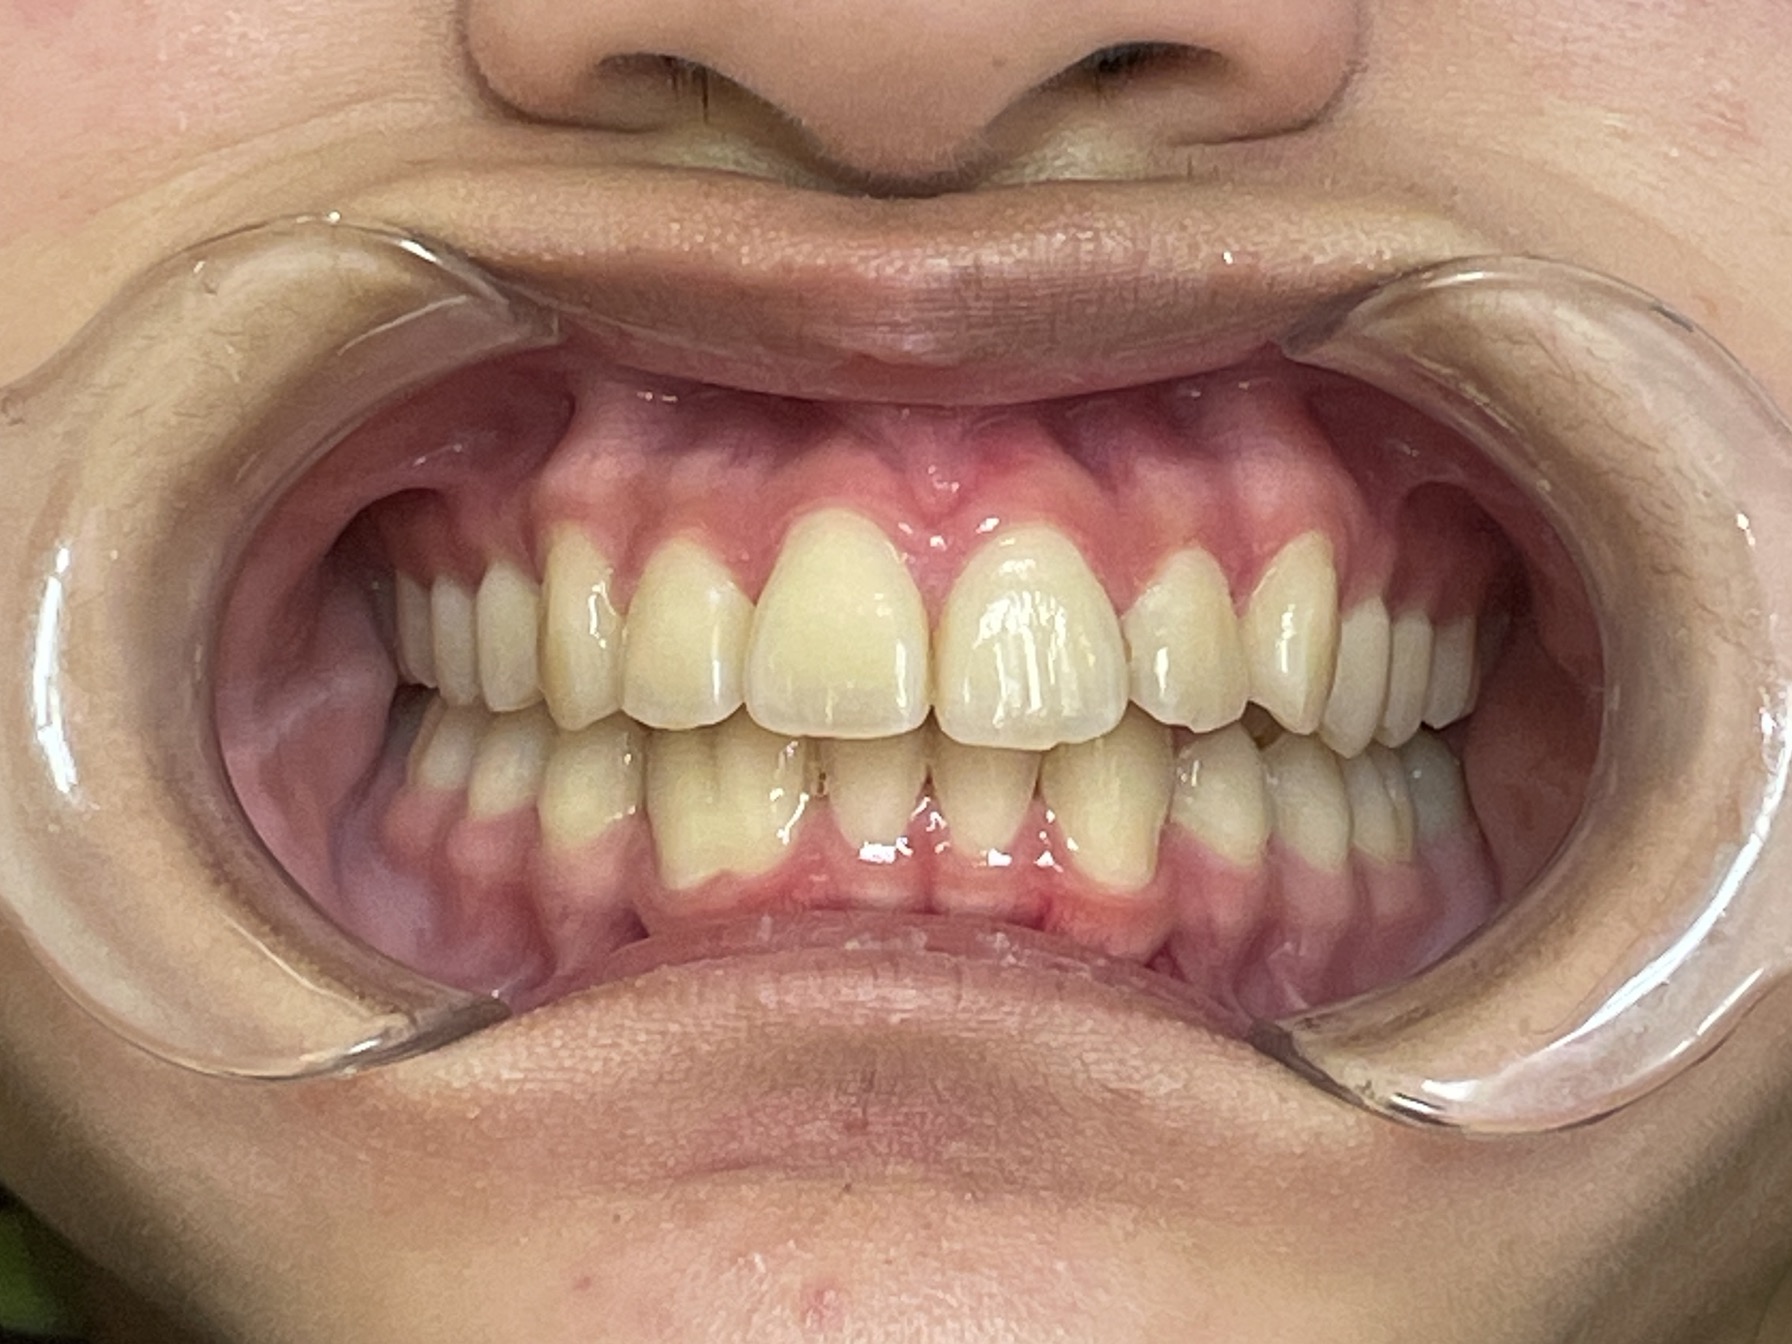

歯がまっすぐ並び、口が閉じやすくなったことで歯ぐきの炎症も改善しました。

患者様にも「歯並びを気にせず過ごせるようになり、笑顔が増えた」と大変お喜びいただきました。

現在は歯並びの後戻りを予防するための「保定装置」をご使用いただき、定期的な経過観察をしています。